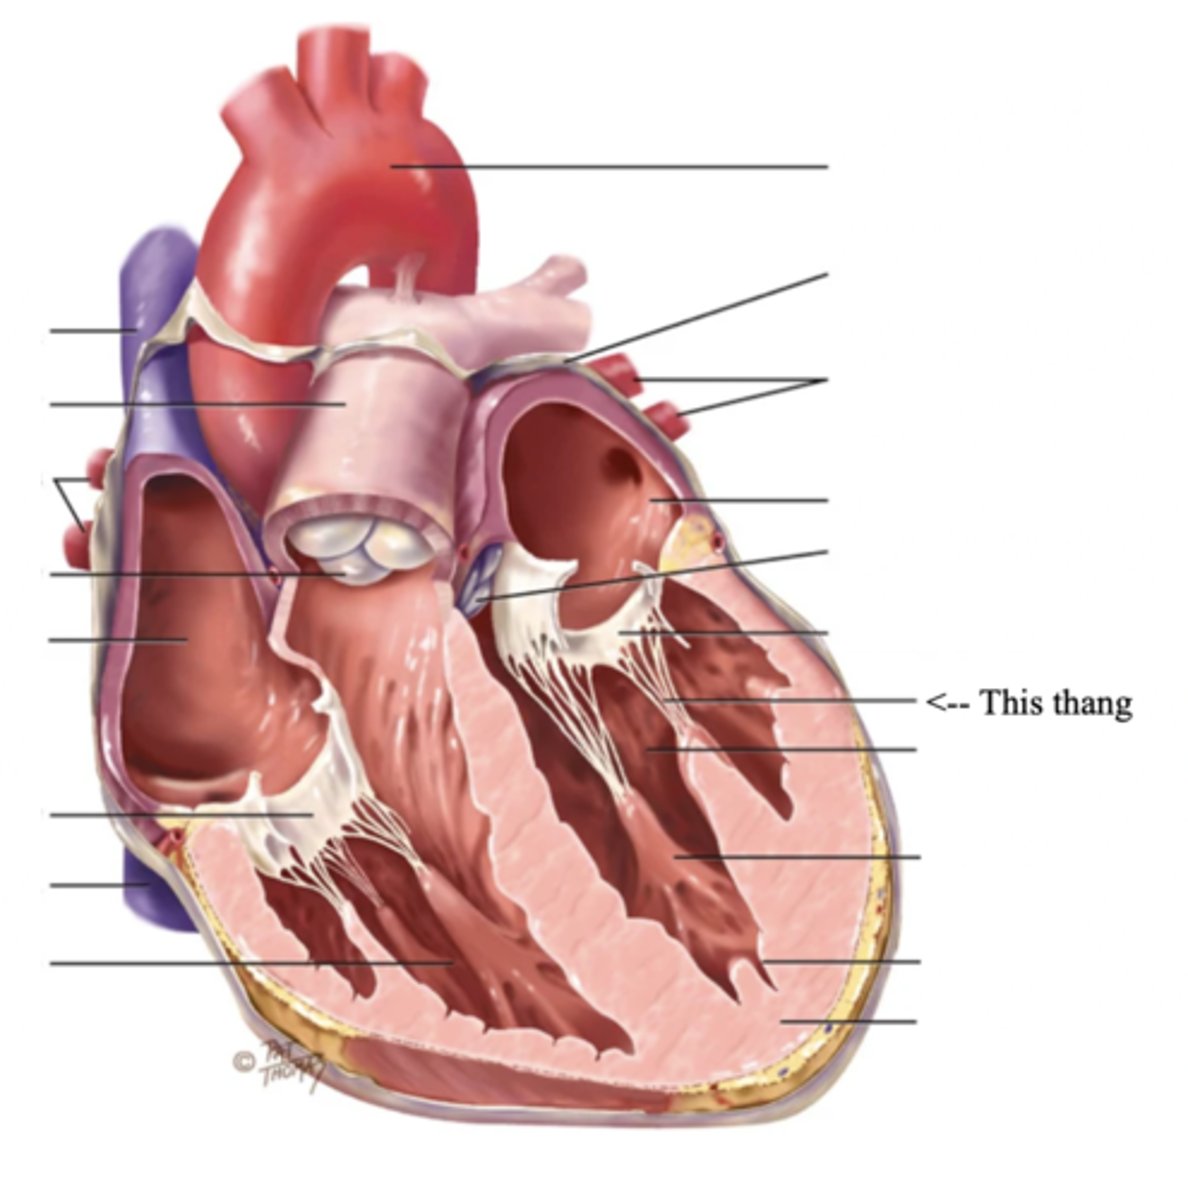

Anatomy of the Heart

Myocardium

The muscular wall of the heart; does the pumping

Endocardium

The thin layer of endothelial tissue that lines the inner surface of the heart chambers and valves

2 Types of Chambers in the Heart

- Atrium

- Ventricles

Atrium (2)

A thin-walled reservoir for holding blood, located at the upper chamber of the heart

Ventricle (2)

The thick walled muscular pumping chamber of the heart located at the bottom chamber of the heart

2 Main Types of Valves of the Heart

- Atrioventicular

- Semilunar

Atrioventricular Valves (AV) (2)

The valves that separate the atria and the ventricles

The 2 Atrioventicular Valves of the Heart

- Tricuspid

- Mitral

Tricuspid Valve

- The right AV valve separating the right atrium from the right ventricle

- Connected by 3 chordae tendinae

Mitral (Bicuspid) Valve

- The left AV valve separating the left atrium from the left ventricle

- Connected by 2 chordae tendinae

Chordae Tendinae

Fibers (heart strings) attatched to the tricuspid and mitral valve which pull it closed when papillary muscles contract, preventing back flow of blood

Semilunar Valves (SV) (2)

Valves located between the ventricles and the pulmonary arteries and aorta

The 2 Semilunar Valves of the Heart

- Pulmonic

- Aortic

Pulmonic Valve

The SV valve of the right side of the heart

Aortic Valve

The SV valve of the left side of the heart